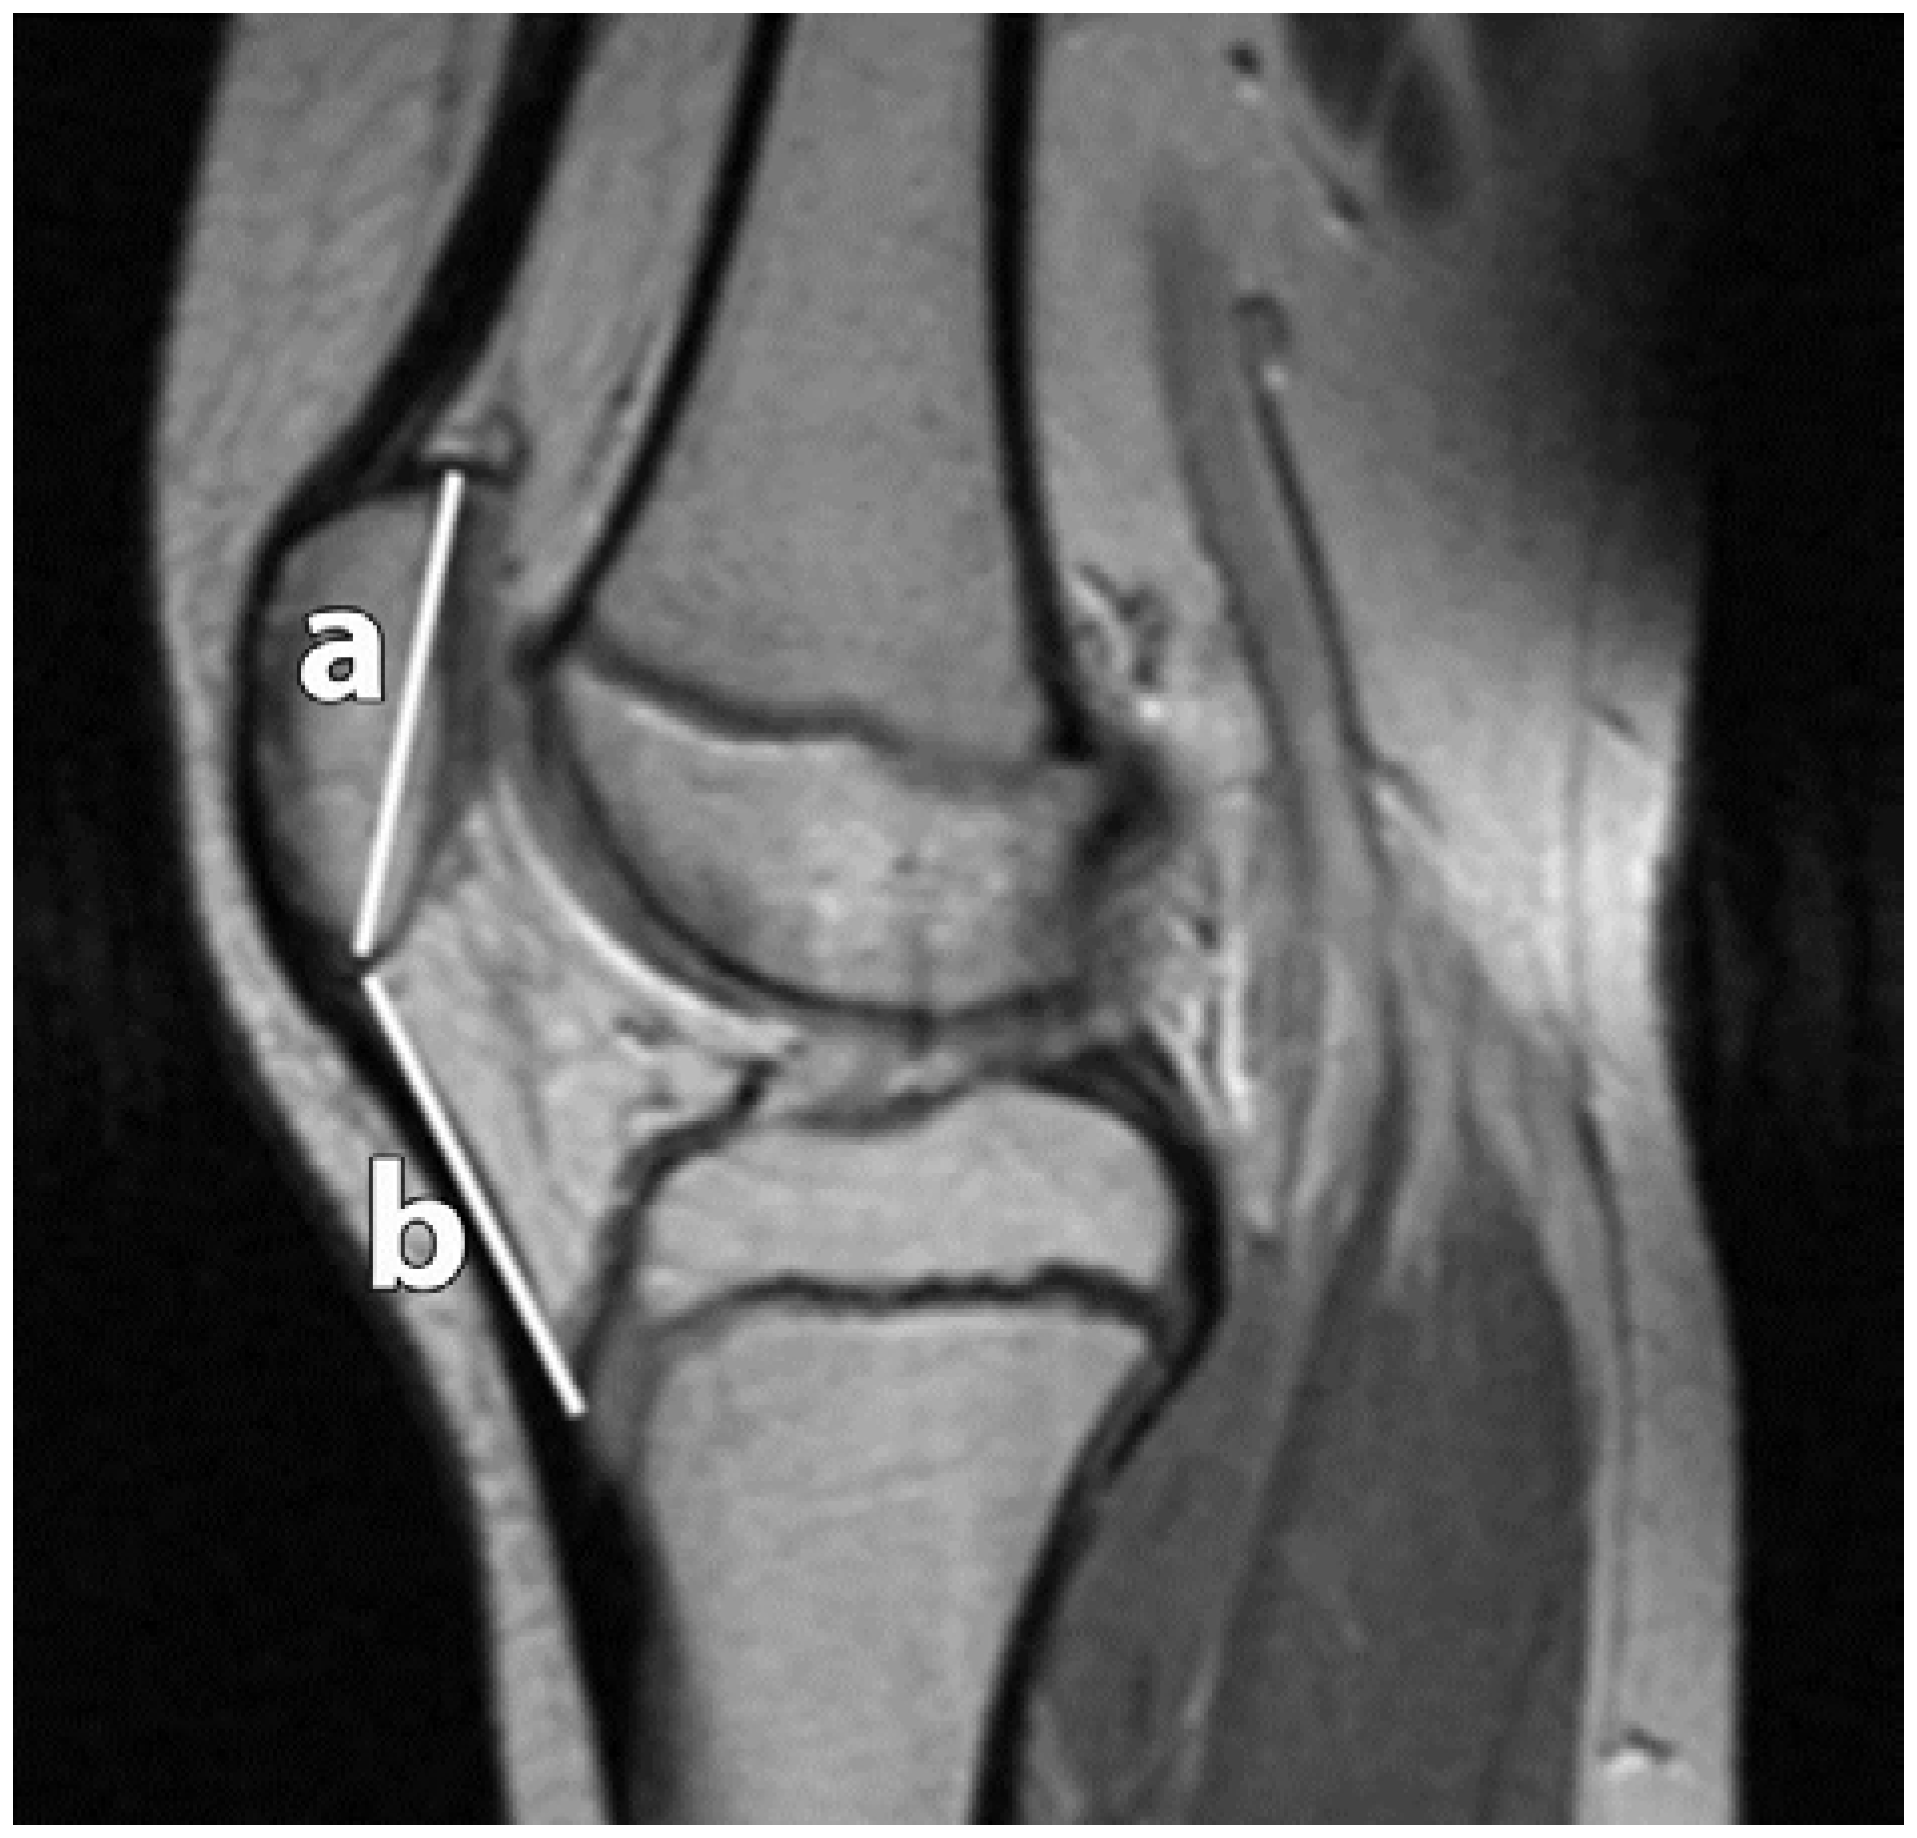

Figure 6.

Patellar Height Ratio (PHR) according to Insall-Salvati. Two measurements were recorded, the distance between the superior apex (articular surface) and inferior apex (non-articular surface) (a); and the distance of the patellar tendon at its attachments from the inferior patellar apex to the tibial tuberosity (b).